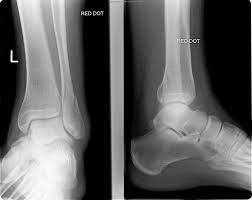

These fractures are classified as 44a3 or 44b3 under the arbeitsgemeinschaft für osteosynthesefragen, ao classification 12 , 13 . Lateral malleolus fractures cause pain, swelling, and bruising around the ankle. Ankle fractures are the most common fractures of the lower extremity. Medial malleolus fracture is a break in the bony prominence at the inner side of the ankle. It describes ankle fracture classification, ankle fracture dislocation.

The herscovi classification is a system of categorizing medial malleolus fractures of the distal tibia based on level. Ankle fractures are the most common fractures of the lower extremity. Lateral malleolus fractures cause pain, swelling, and bruising around the ankle. One option involves inserting screws that run from the front to the back of the ankle or the other way around. Posterior malleolus fracture component 9 , 10 , 11 . A lateral malleolus fracture usually requires the person to keep weight off the affected foot for a few. Although a medial malleolus fracture can be a serious injury, the outlook for recovery is good, and complications when a medial malleolus fracture occurs by itself, it's called an isolated fracture. There is the medial malleolus with the deltoid complex (1) and the lateral malleolus with the lateral ligaments (2).

There are two major classification systems for ankle fractures.

Mehul mayank1, prof jike lu2, jac trappel3 & malleolus fracture. There are two major classification systems for ankle fractures.